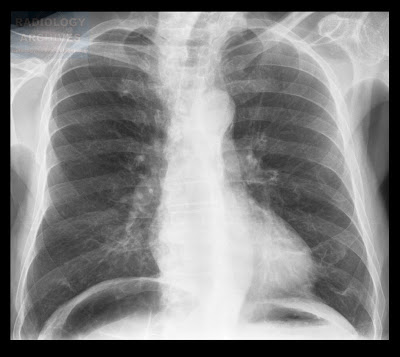

πλάγιο ακτινογράφημα. Ατελεκτασία δεξιού μέσου λοβού. η μικρή μεσολόβιος έχει μετακινηθεί προς τα κάτω και η μεγάλη προς τα πάνω, σχηματίζοντας μια σφηνοειδή σκίαση.

Διαλείπουσα ((σύνδρομο Brock) ή σταθερή ατελεκτασία του δεξιού ή αριστερού μέσου λοβού, απότοκη εξωαυλικής (λόγω πιέσεως από λεμφαδένες) ή ενδαυλικής (π.χ., ενσφήνωση ξένου σώματος) αιτιολογίας αποφράξεως του προσαγωγού βρόγχου. Ο δεξιός μέσος λοβός είναι μακρύς και λεπτόφυής, και έχει εξαιρετικά πτωσή παροχέτευση και ελλειπή κάθαρση, συγκριτικά με όλους λοβούς του πνεύμονος, με ποτέλεσμα να είναι επιρρεπής στην παγίδευση βυσμάτων και την απόφραξή του. Συχνά διατρέχει ασυμπτωματικά, αν και μπορεί να περιγράφονται επανειλημμένα επεισόδια παραγωγικού βήχα και πνευμονίας.

Μπορεί να παραχθεί και χωρίς την προϋπόθεση της αποφράξεως του μέσου λοβαίου βρόγχου, λόγω φλεγμονωδών εξελίξεων διαχρονικά που απέλειξαν σε δομικές αλλοιώσεις και την εγκατάσταση ελλειμμάτων στο τοίχωμα του βρόγχου και τον παράπλευρο αερισμό του λοβού. Στις περισσότερες των περιπτώσεων αναγνωρίζονται εντοπισμένες βρογχεκτασίες, που μπορεί να είναι απότοκες ή αίτιο του συνδρόμου[i].